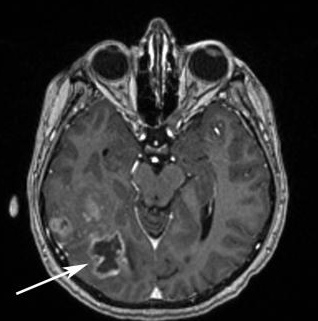

- Компьютерная томография (КТ) (с целью полного анализа подробного изображения мозга).

- Магнитно–резонансная томография (с целью полного анализа подробного изображения мозга).